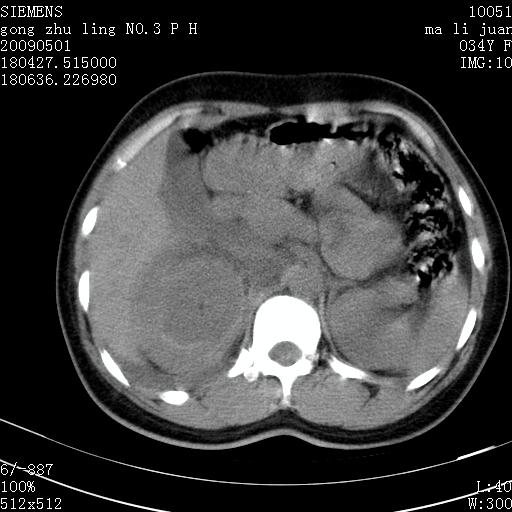

标题: CT19733:右肾碎裂 [打印本页]

标题: CT19733:右肾碎裂

青年女性,骑摩托车摔伤。

右肾碎裂伤,包膜下血肿。

术中仅见右肾碎裂,肾蒂血管未见断裂。